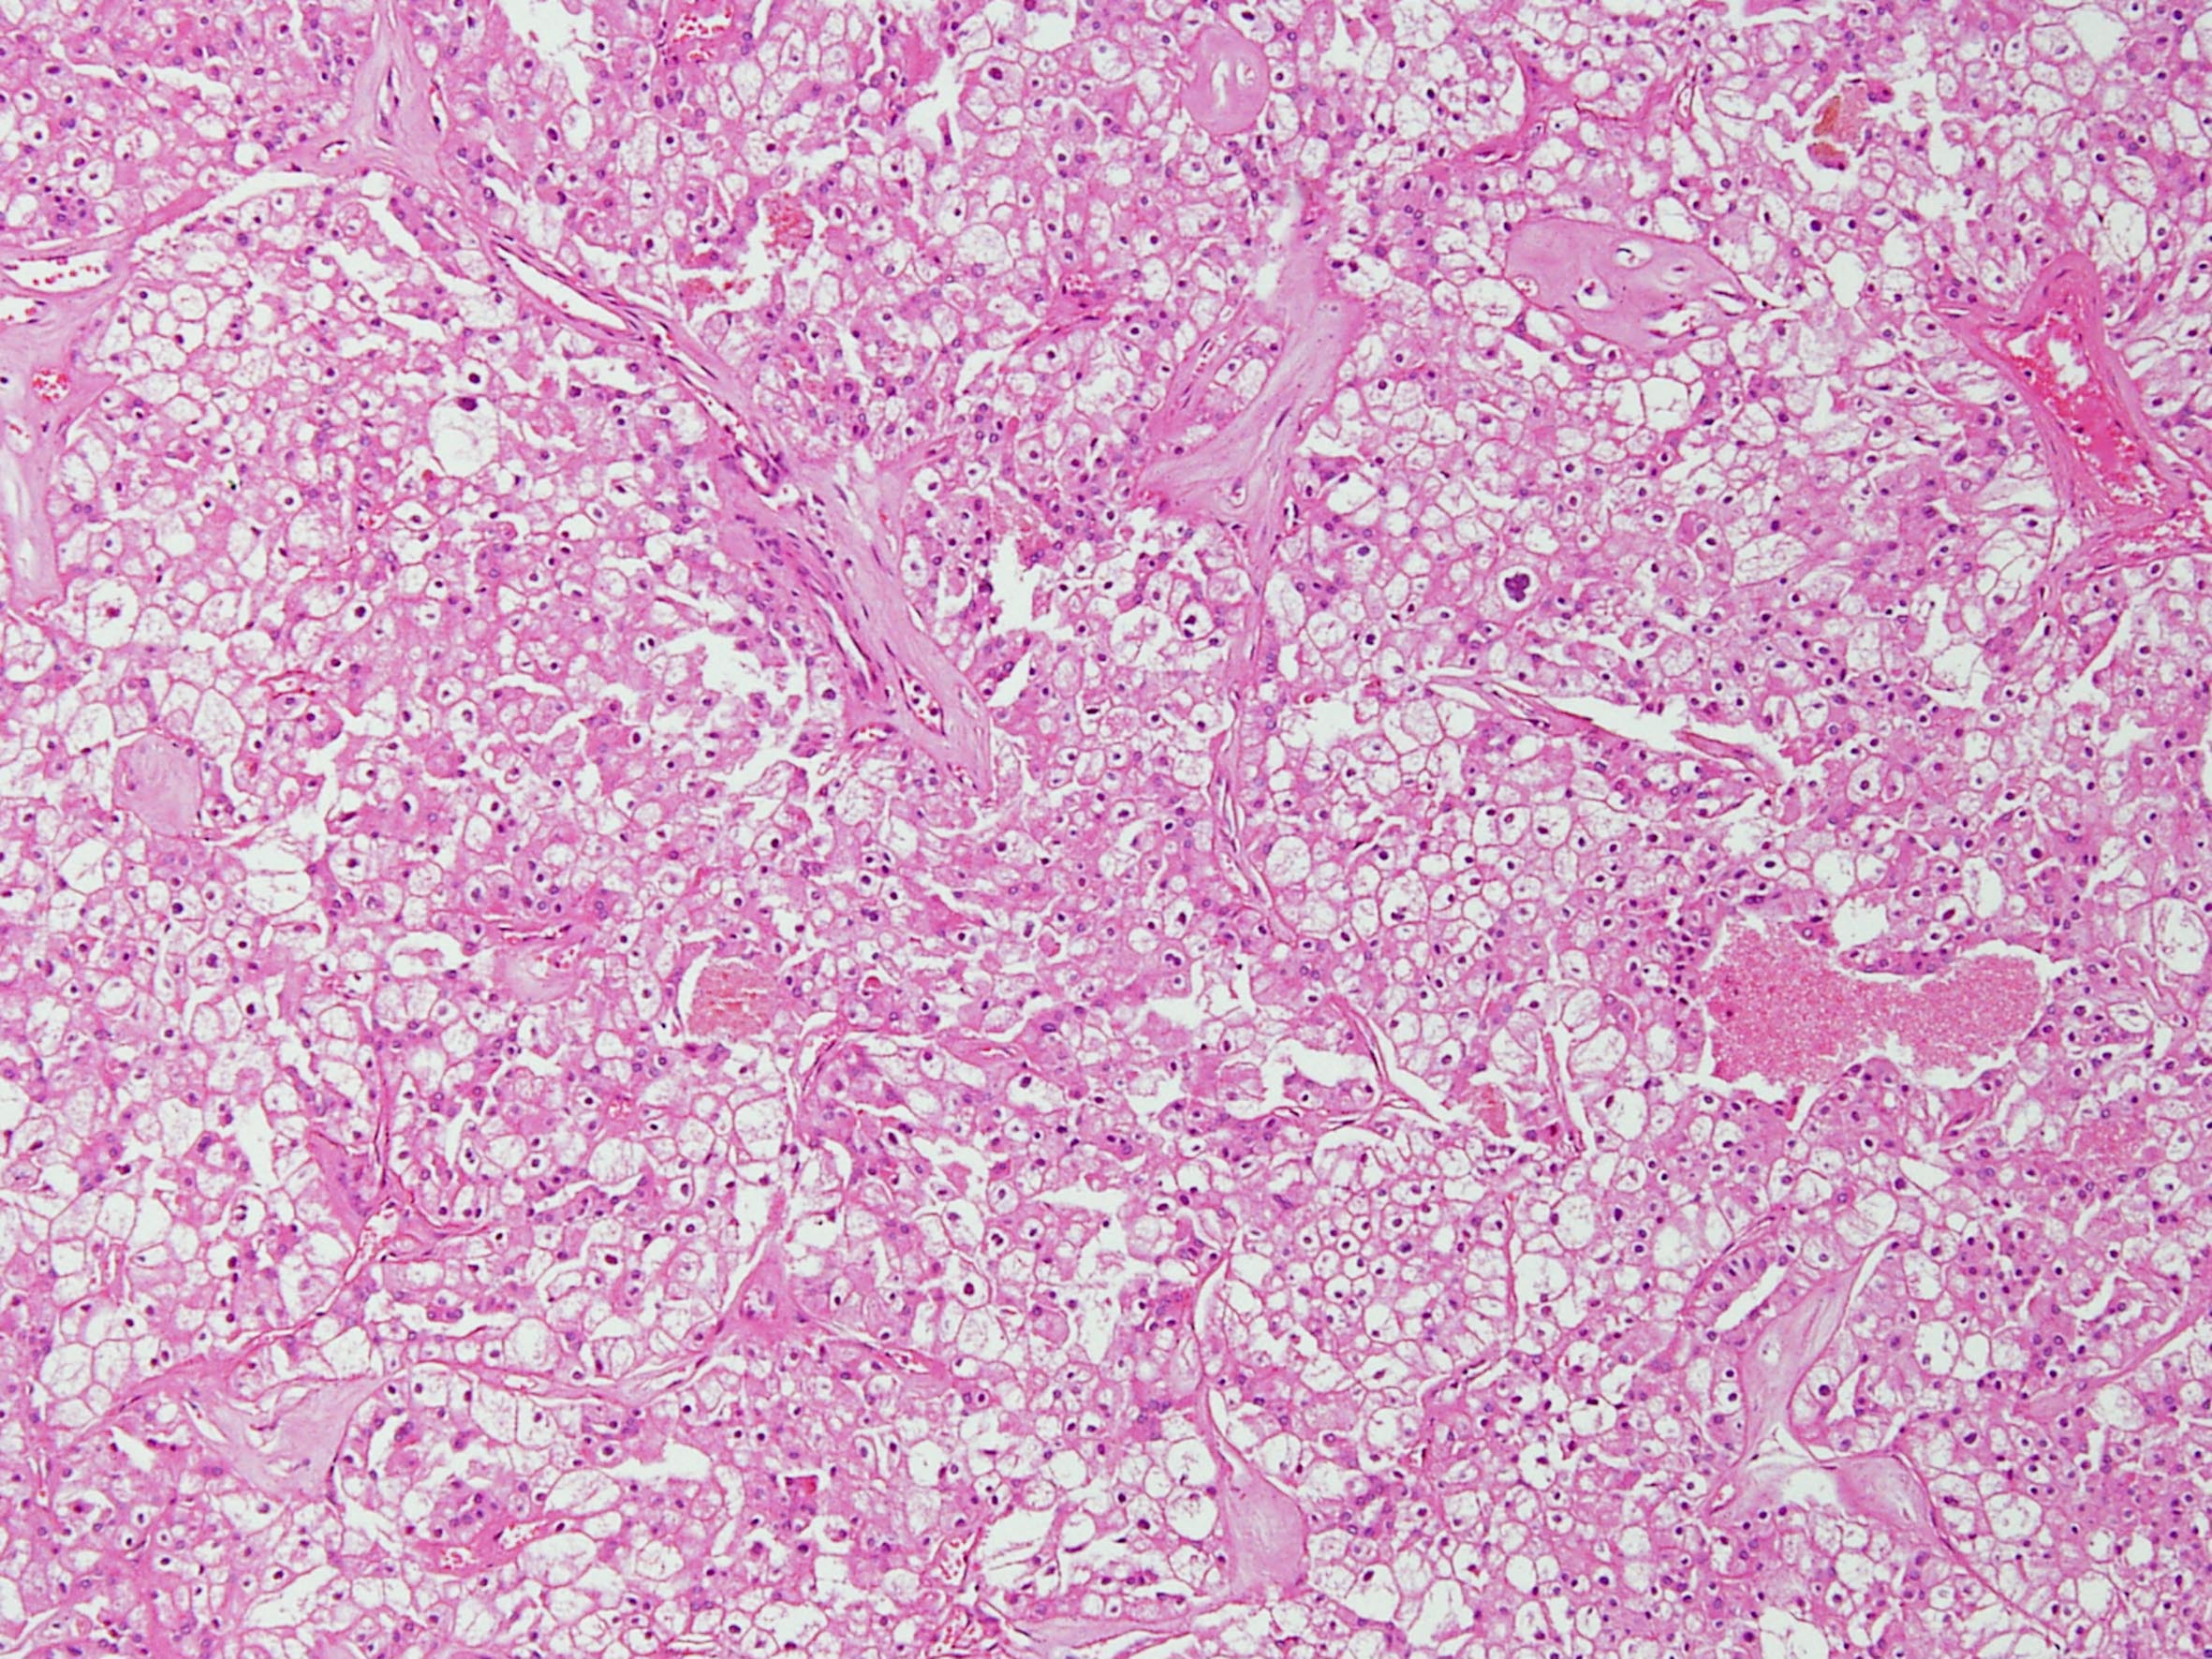

Chromophobe renal cell carcinoma